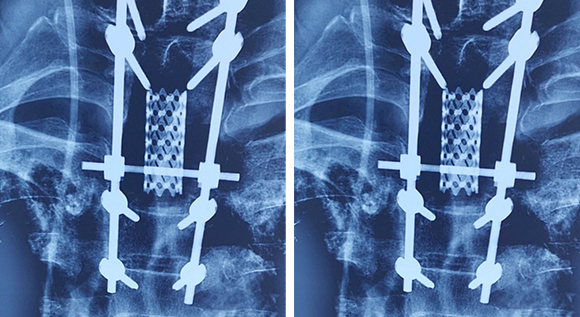

脊柱脊髓神经微创中心以微创技术为引领,以功能恢复为目标,主要治疗脊柱外伤、肿瘤、退行性病变、脊柱畸形等疾病。团队利用神经外科显微技术,结合神经内镜微创技术,对脊柱间盘变性疾病、颈腰椎管狭窄、颈腰椎间孔狭窄、颈腰椎间盘突出、颈腰椎体不稳、脊柱骨折、寰枢椎脱位、脊柱肿瘤、椎管内肿瘤、脊髓损伤、脊髓空洞、脊髓栓系等疾病进行高效、特色手术治疗,如颅颈交界区畸形寰枕减压内固定术、脊柱肿瘤全脊椎切除内固定术、微创椎管内肿瘤切除术、微创脊柱旁肿瘤切除术、寰枢椎脱位椎间融合内固定术、脊柱骨折微创经皮椎弓根钉内固定术、经椎间孔椎间融合内固定术(MIS—TLIF)等,最大程度降低脊柱脊髓手术创伤,具有创伤小、输血少、恢复快、口碑好,出院早等优势。